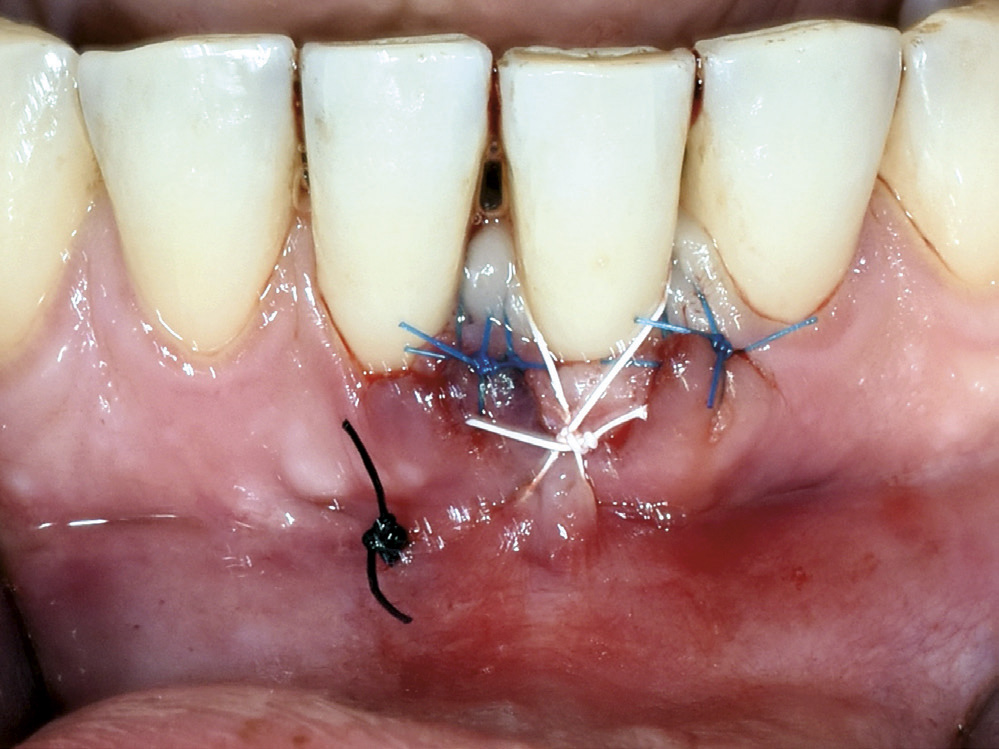

Ein kirurgisk korreksjon med bruk av «konvolutt-teknikk» og ganetransplantat vart tilrådd som behandling for å dekka den labiale retraksjonen 31. Dette behandlingsalternativet vart diskutert med pasienten og ho samtykte. Etter å ha planert rotoverflata på 31, vart marginalt vev mobilisert og lomma utvida apikalt og lateralt utan vertikale hjelpesnitt (figur 5 A). Det vart så lagt eit horisontalt snitt tilsvarande breidda på transplantatet langs palatinale tannrekke regio 24, 25 og deretter to vertikale snitt mot midten av ganen med ei lengde som svara til høgda på transplantatet. (figur 5 B). Det underliggjande bindevevslaget vart fridissekert og transplantatet plassert i blautvevslomma labialt på 31 slik at heile retraksjonen vart dekka (figur 6). Transplantatet vart så stabilisert med ikkje-resorberbare suturar. Ganeepitelet vart replassert og primær sårlukking sikra med enkle suturar. Suturane vart fjerna 13 dagar postoperativt.

Figur 5 A. Kirurgisk mobilisert blautvevslomme labialt 31.

Figur 5 B. Hausting av transplantat frå ganen regio 24,25.